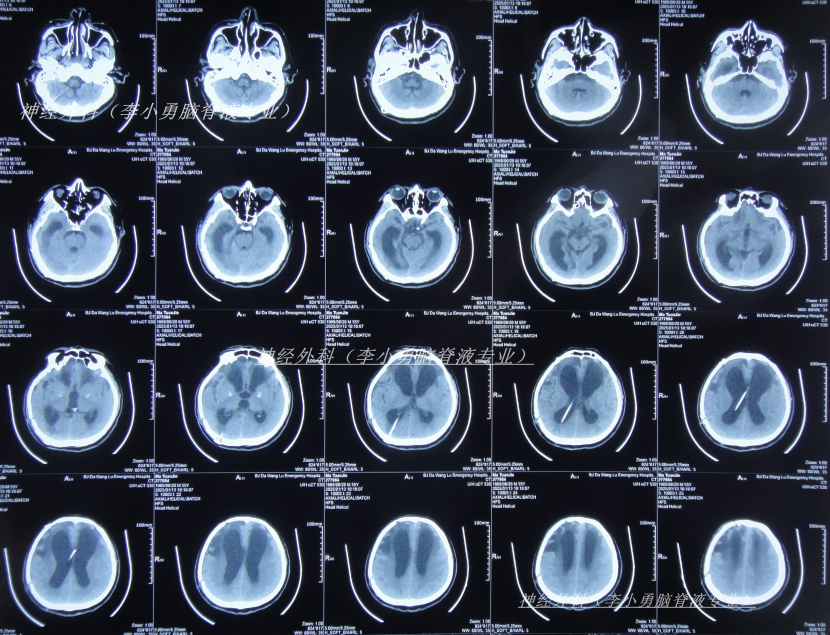

脑室腹腔分流术后13天即2024年10月2日,查头颅CT示去骨瓣术后,脑室分流术后状态,脑室仍有扩张(图-1);但意识有好转。

图-1:2024年10月2日头颅CT

脑室腹腔分流术后22天即2024年10月11日,查头颅CT示脑室缩小(图-2)。

图-2:2024年10月11日头颅CT

脑室腹腔分流术后28天即2024年10月17日,进行了颅骨修补术(图-3)。

图-3:2024年10月18日头颅CT

颅骨修补术后5天即2024年10月22日(脑室腹腔分流术后33天),查头颅CT示颅骨修补术后状态(图-4)。

图-4:2024年10月22日头颅CT

颅骨修补术后10天即2024年10月27日(脑室腹腔分流术后38天),可以自行站立,搀扶下能走,查头颅CT(图-5)后转至某康复医院。

图-5:2024年10月27日头颅CT

因症状没有改善,决定到北京就诊,经过考虑在李小勇脑脊液专业和北京某三甲医院,选择了北京某三甲医院,2025年1月10日(颅骨修补术后85天即脑室腹腔分流术后113天),住入北京某三甲医院,查头颅CT(图-6)和腰穿检查后考虑颅内感染,给予抗感染治疗。

图-6:2025年1月10日头颅CT

治疗4天后即2025年1月13日,仍发热,查头颅CT(图-7)和肺部CT(图-8)后继续抗感染治疗。

图-7:2025年1月13日头颅CT

保守治疗1周没有效果,于2025年1月18日(颅骨修补术后93天即脑室腹腔分流术后121天),再次选择了北京另一所三甲医院,查头颅CT(图-9)后急诊留观,行脑脊液检查提示人类疱疹病毒。

图-9:2025年1月18日头颅CT

该院治疗10天即2025年1月27日,查头颅CT示脑室进一步扩张(图-10)。

图-10:2025年1月27日头颅CT

入院当天查头颅CT示颅脑术后改变,脑室扩张,双侧额部硬膜下积液(图-12);胸部CT示两肺炎性病变,心包积液,双侧胸腔积液(图-13)。

图-12:2025年2月4日头颅CT

图-14:2025年2月4日术后头颅CT

住院治疗5天即2025年2月8日,查头颅CT示脑室有缩小(图-15)。

图-15:2025年2月8日头颅CT

图-17:2025年3月4日头颅CT